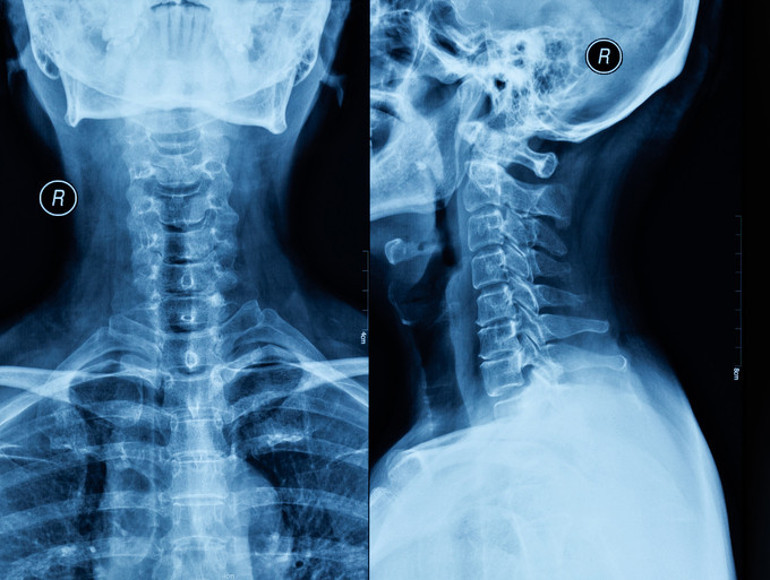

Hayley, “Çok çılgıncaydı. Esnemenin kuvvetiyle C6 ve C7 omurları omuriliğime doğru fırlamıştı. Bunun çok nadir görülen bir olay olduğunu söylediler” dedi.

Omurgada kafatasını destekleyen yedi adet servikal omur bulunur. Black’in yerinden çıkan omurları, üst uzuvların hareketinden sorumlu sinirlerle bağlantılıdır.

Neyse ki, tıbbi olarak ‘diskektomi ve füzyon’ olarak bilinen acil ameliyat başarılı oldu.

Cerrahlar hasarlı diskleri çıkardı ve boynunu metal bir plakayla kaynaştırdı, bu da trakea izi bıraktı.